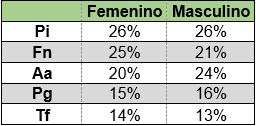

No se detectaron diferencias significativas en la proporción de microorganismos al considerar el sexo con un nivel de significación de 0.05 utilizando la prueba T para dos muestras suponiendo varianzas iguales (Tabla 4).